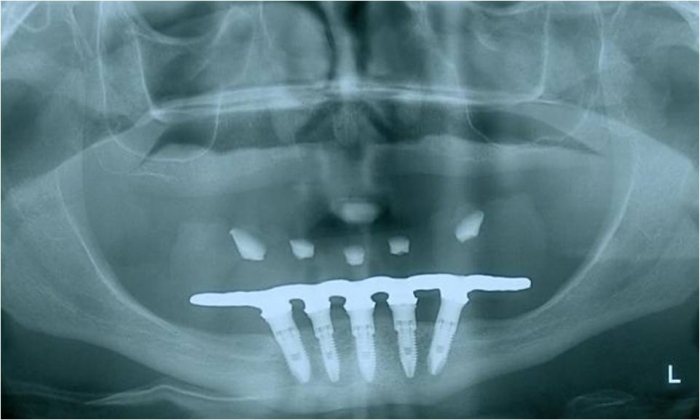

Raio x final

Prótese fixa inferior em resina